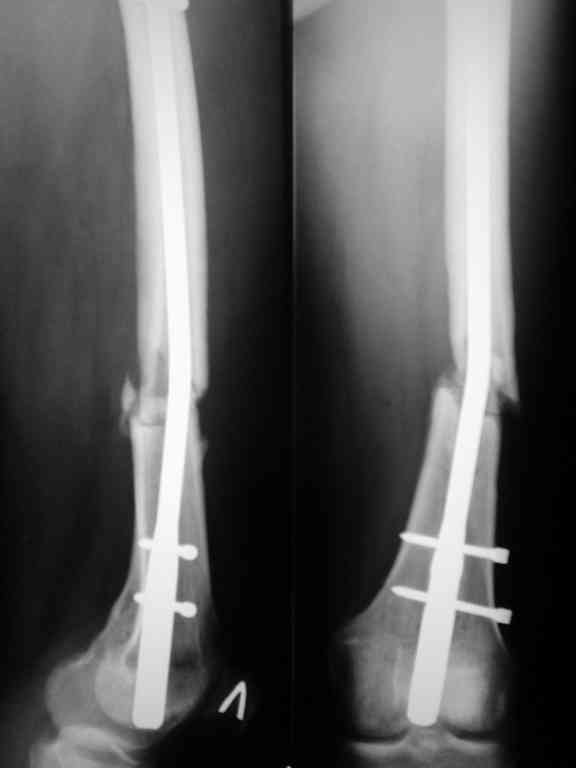

Соматически здорова. В ноябре 2004 года падение с высоты 12 м, перелом правой вертлужной впадины со смещением, неврит седалищного нерва, откр. перелом дистального отдела большеберцовой кости справа и закрытый перелом с/н/3 левого бедра. К нам поступила через 3 недели после травмы, был выполнен в 2 сессии сначала интрамедуллярный ретроградный остеосинтез бедра слева, затем остеосинтез вертлужной впадины и голеностопа справа. При остеосинтезе бедра пришлось немного приоткрыться в зоне перелома для репозиции и вообще операция затянулась часа на 2.5-3 (это один из наших первых интрамедуллярных синтезов). Через 4 месяца при нагрузке весом около 50 кг постепенно развилась варусная деформация бедра с искривлением стержня. Закрыто выпрямили под наркозом, динамизация гвоздя,но в сентябре 2005 г. согнулось бедро снова. Гвоздь удалили, остеосинтез пластиной, декортикация, пластика спонгиозой из метафиза б/берцовой кости. Динамика заживления вялая, но конструкция стояла неплохо (без признаков расшатывания), постепенно дали нагрузку - в марте 2006 года - перелом пластины - реостеосинтез пластиной, пластика гребнем подвздошной кости. На контролях (за август, т.е. 4 мес. после операции - прилагаю) динамика положительная, разрешена нагрузка до 50 кг. В начале этой недели без падения вновь появились боли в бедре - на Р-граммах - перелом пластины (снимки прилагаю). Фоном ко всему этому то, что и перелом вертлужки и дистального отдела б/б кости тоже не срастаются, хотя на голени уже дважды выполнялась костная пластика, на впадине - вторичное смещение, перелом части металлоконструкций. Исследовали гормональный фон - парат-гормон и прочие щитовидные в норме, месячные регулярно.Прошу совета по тактике дальнейшего лечения и выяснения причины тотального несращения всего сломанного.

Уважаемый Александр. Случай достаточно интересный, поскольку за 2 года,почему то ничего не срастается и все ломается. Жаль нет рентгенограмм таза и голени.Основными причинами несращения переломов бывает 1.не правильно выбранная тактика лечения, в том числе тактика оперативного лечения ( к примеру - не тот фиксатор, не того размера, неправильно установлен и т.д.)2.Девитализация костных отломков, а судя по рентгенограммам старались вы на совесть, когда открывали область перелома при интрамедуллярном остеосинтезе. Кстати, если это был не блокируемый остеосинтез, а обычный, то понятно почему стержень согнулся и нет сращения. На представленных рентгенограммах отдельные винты расположены даже с внутренней стороны, т.е. открылись вы качественно. 3.не правильно выбранная тактика лечения в п.операционном периоде или не выполнения больным данных рекомендаций. По бедру - мы бы убрали пластину и выполнили ретроградный блокируемый остеосинтез с рассверливанием. Если нет возможности, есть аппарат Илизарова. Но мороки и для вас и для больного много.